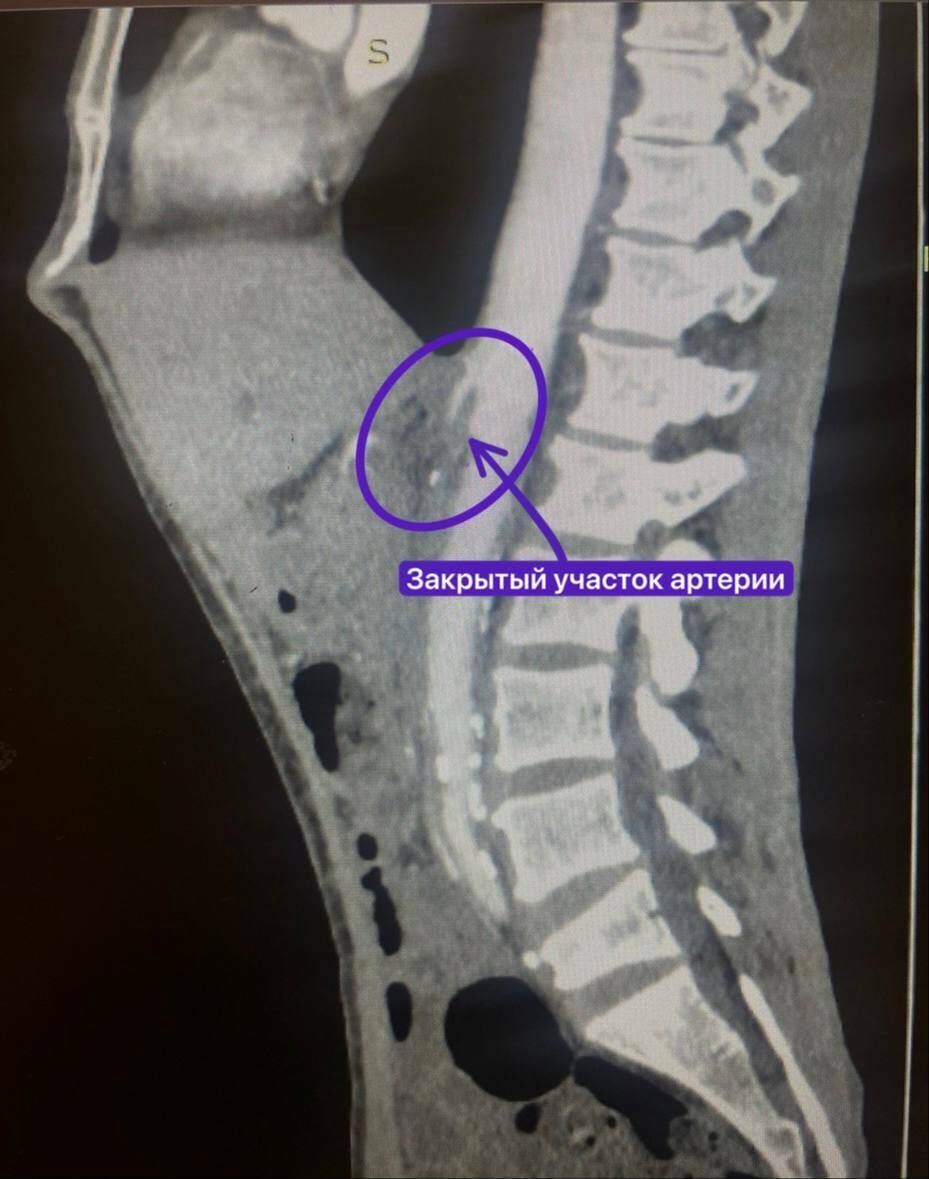

У мужчины из-за атеросклероза бляшки закрыли верхнюю брыжеечную артерию. Обычно в таких случаях в артерию под контролем рентгена хирурги ставят стент.

Из-за того, что артерия закрылась совсем, рентген-хирурги не смогли провести через нее проводником. Мужчину перевели в сосудистое отделение, где хирурги взялись за протезирование артерии.